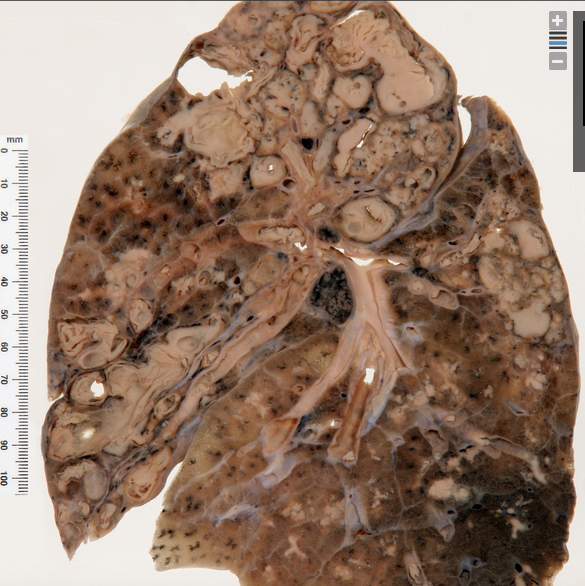

Emphysema, small areas of pneumonia in base

Emphysema, bullae